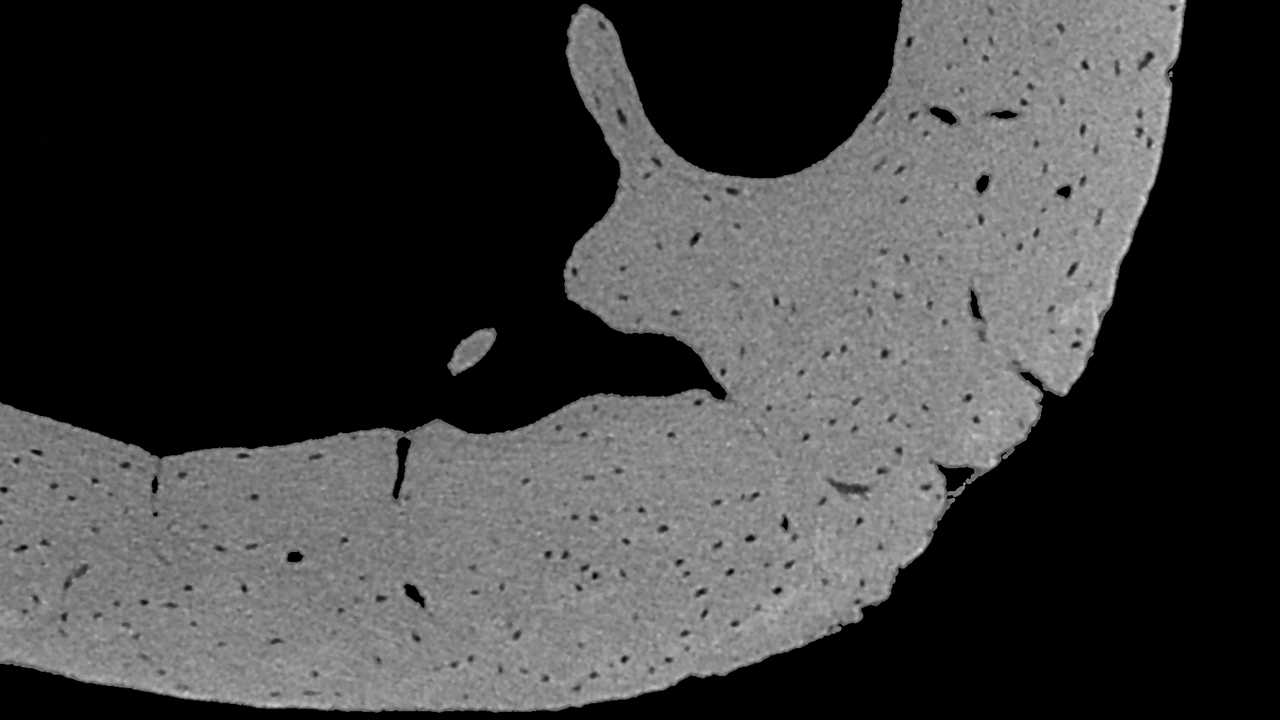

Submicron Imaging of Bone Osteocytes and Vessels

Submicron imaging of mineralised bone opens the field of ultra-structural analysis of bone including the distribution of osteocyte lacunae (spaces) and blood vessel canals.